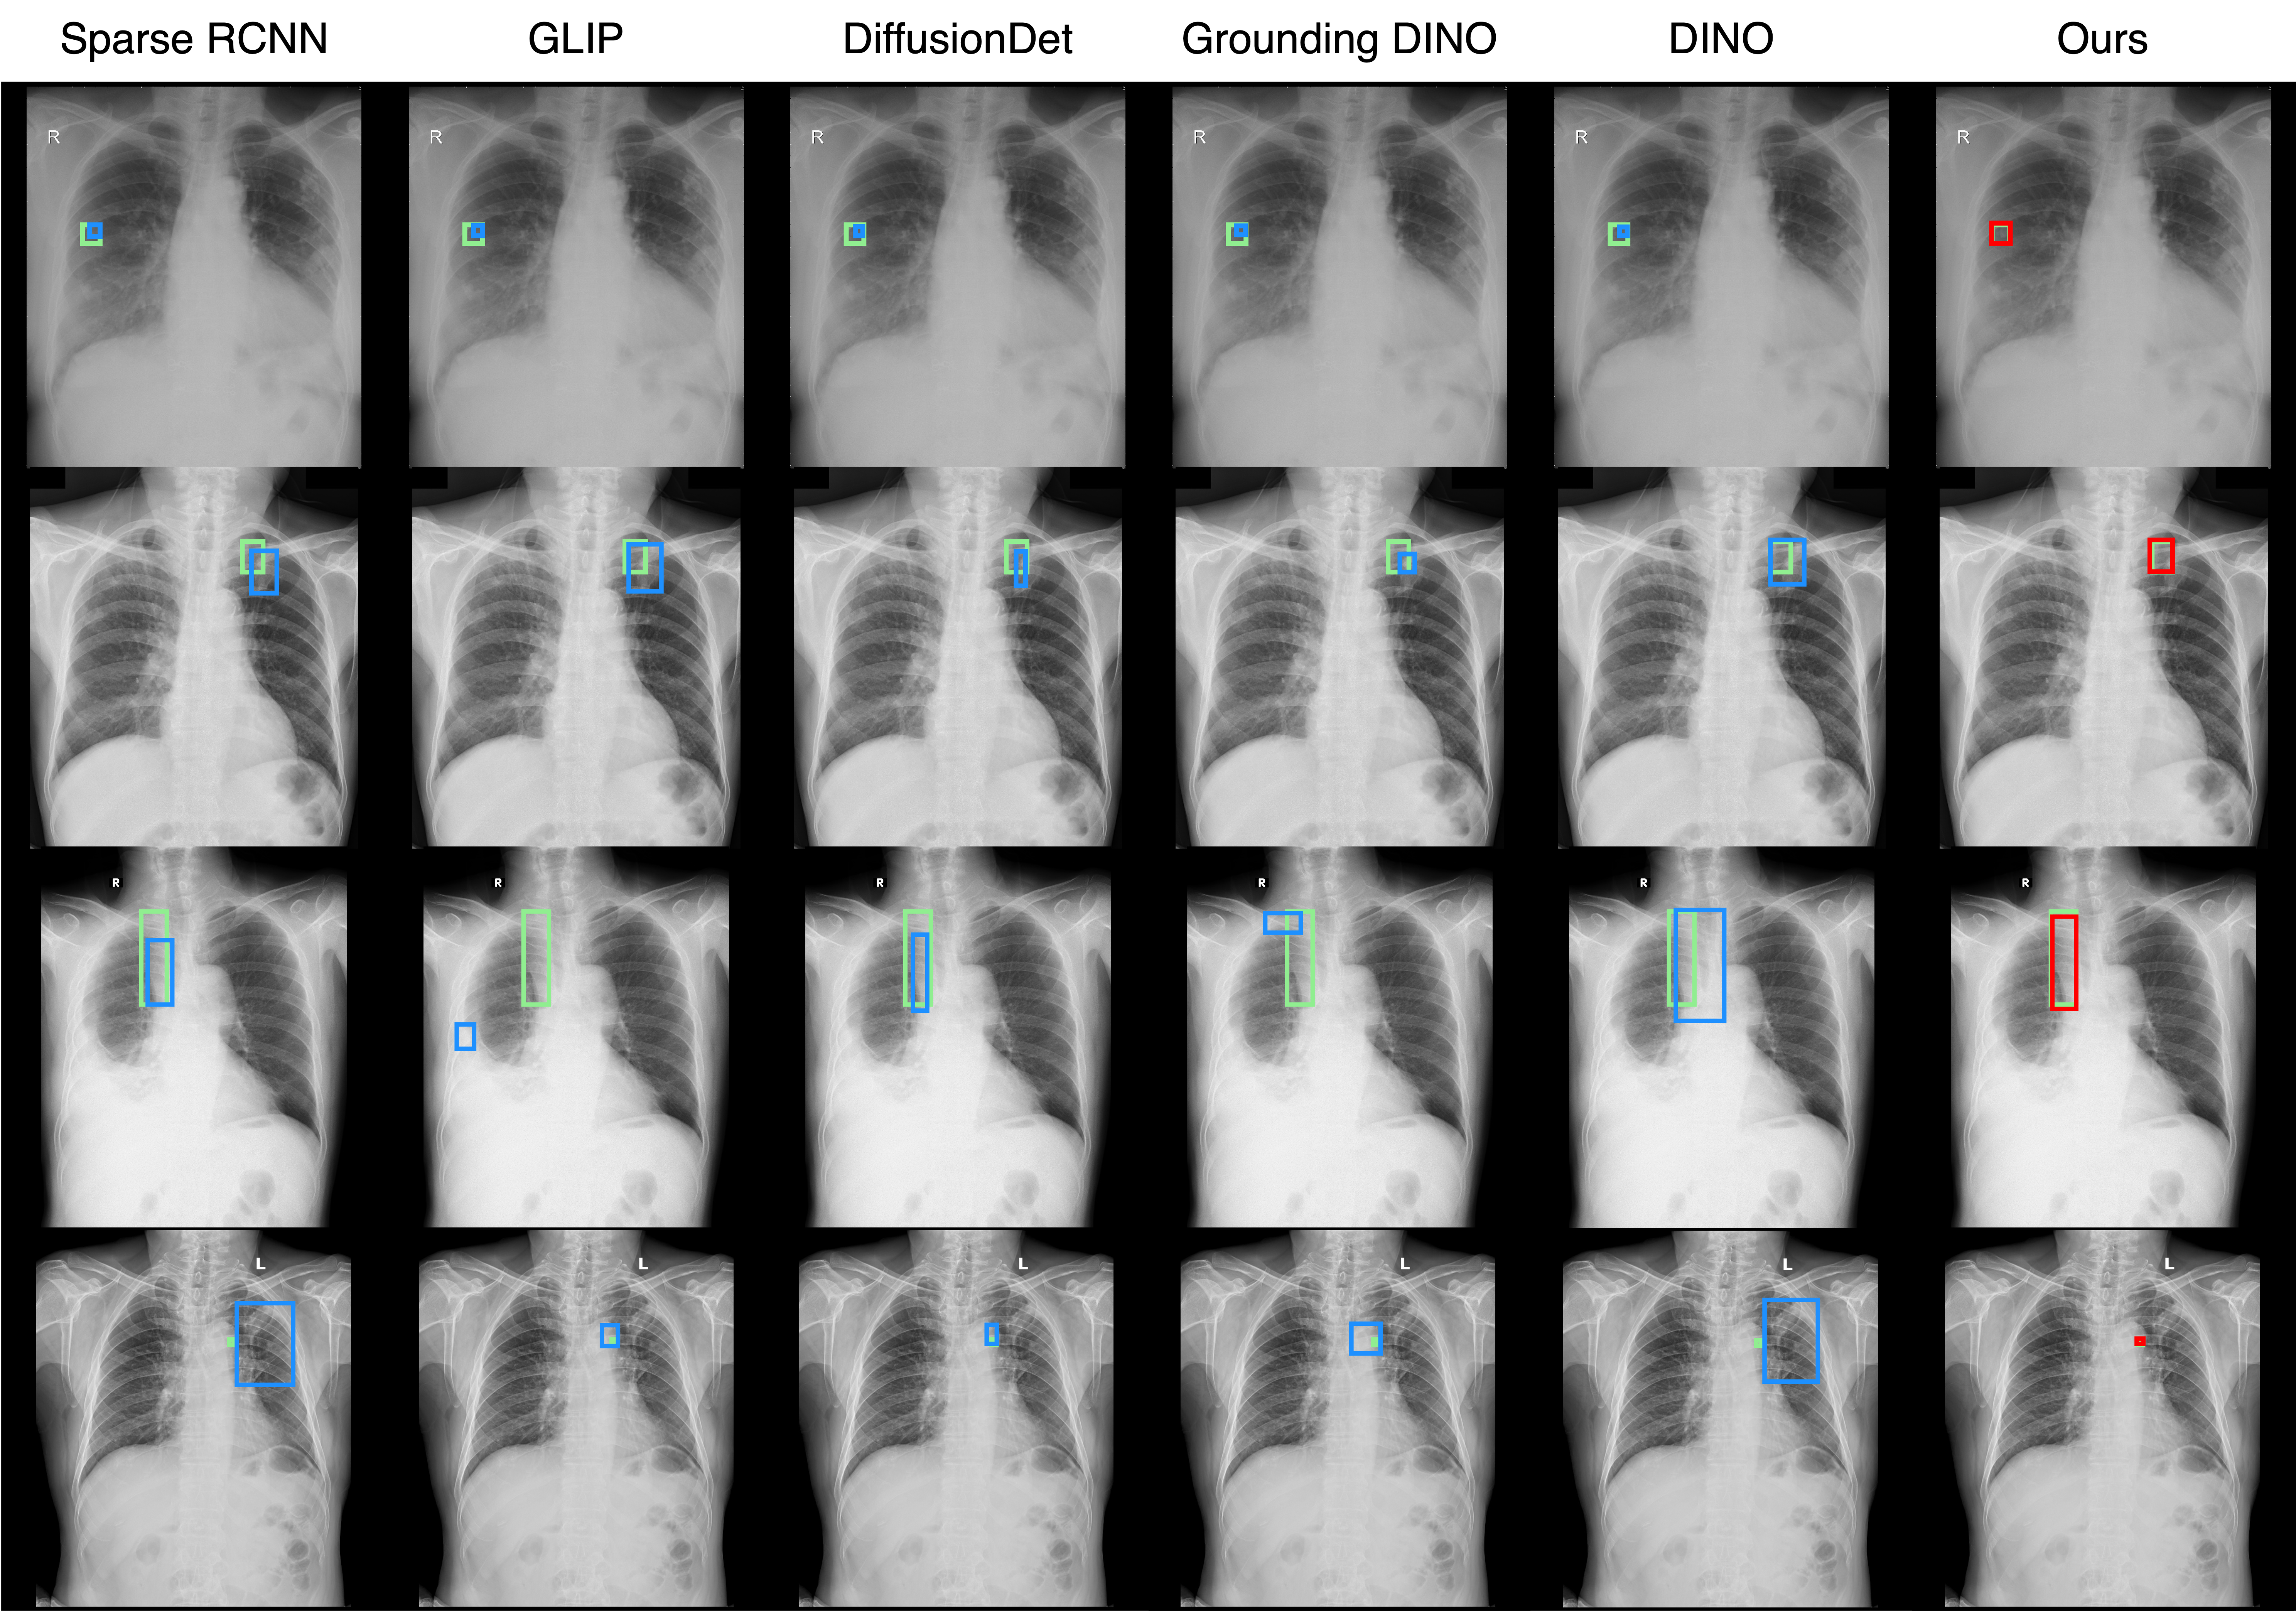

Comparison with other detectors

Qualitative comparison results

Qualitative Comparison. Comparison results between various state-of-the-art detection methods and the proposed method is shown above. Our method effectively leverages modality context to significantly enhance anomaly localization (red), compared to baseline results (blue). Ground truth bounding boxes are green. For cases where the bounding boxes are small, insets show an enlarged view of the highlighted yellow region.